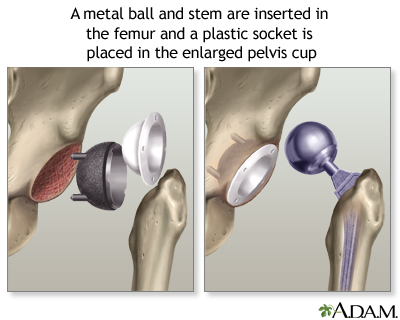

The new hip that replaces the old one is made up of these parts:

- A socket, which is usually made of strong metal.

- A liner, which fits inside the socket. It is most often plastic. Some surgeons are now trying other materials, such as ceramic or metal. The liner allows the hip to move smoothly.

- A metal or ceramic ball that will replace the round head (top) of your thigh bone.

- A metal stem that is attached to the thigh bone to anchor the joint.

- Put the new hip socket in place; a liner is then placed in the new socket.

- Insert the metal stem into your thigh bone.

- Place the correct-sized ball for the new joint.

- Secure all of the new parts in place, sometimes with a special cement.